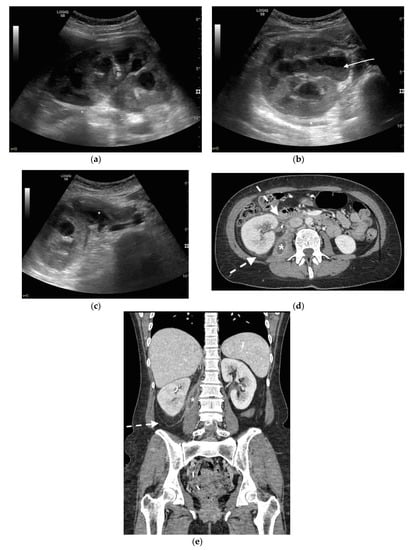

3. Ultrasound

4. CT